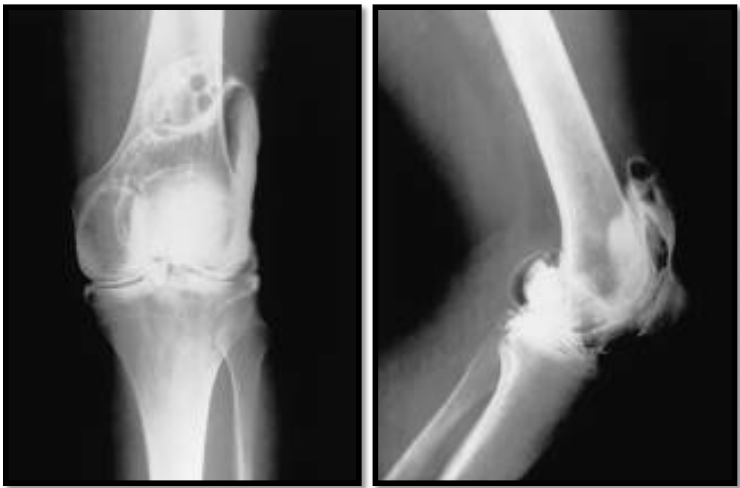

What is seen in this image

A

• AP knee image for meniscal tear

• 30° rotation of knee between exposures

• Six views per image receptor

Left: Torn meniscus

Right: Normal meniscus

MRI has taken over for knee arthogram